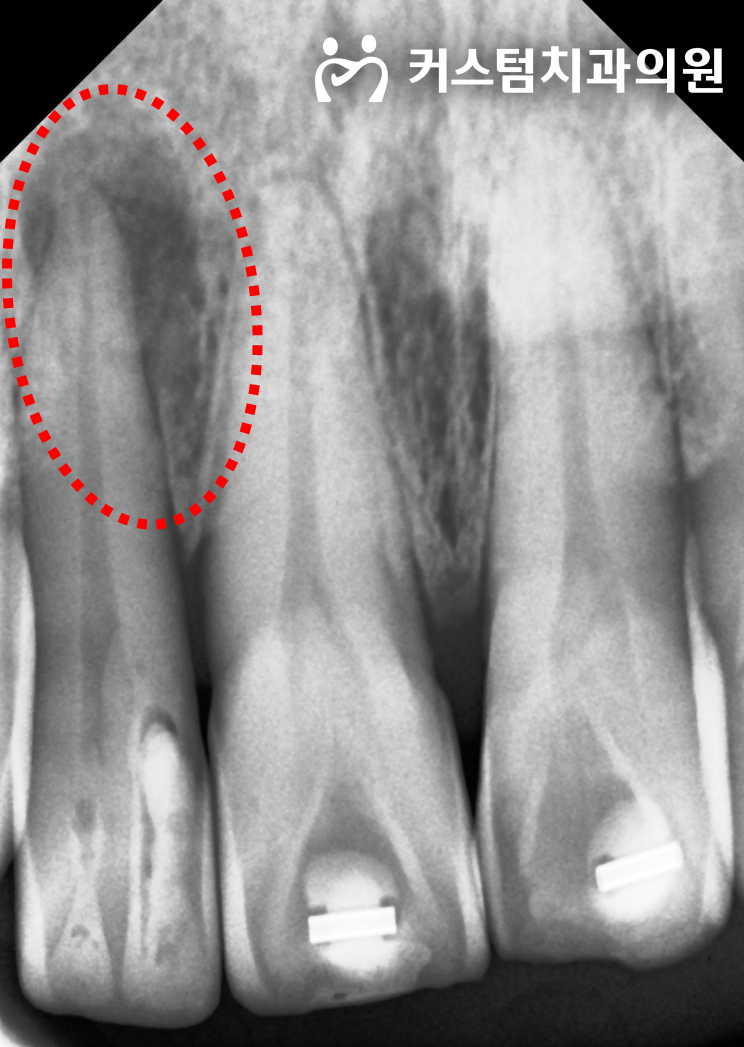

2023년 7월 21일 첫 진료 시 촬영한 방사선 사진입니다.

더 심각한 문제는 방사선 사진에서 확인됩니다.

우측 측절치 뿌리 끝에 잇몸뼈를 광범위하게 녹여버린 치근단 염증 병소가 관찰됩니다.

즉, 치열이 틀어진 진짜 원인은 치아가 삐뚤게 자란 것이 아니라, 뿌리 끝에서 팽창한 염증성 조직이 물리적인 압력을 가해 치아를 바깥쪽으로 밀어냈기 때문이었습니다.

이 상태에서 무리하게 교정 장치를 붙여 치아를 당겼다면, 뼈가 녹아있는 상태이므로 치아가 완전히 탈락(발치)되는 치명적인 결과를 초래했을 것입니다.